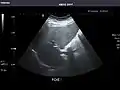

Liver

Liver: Diffusely homogeneous and normal in echogenicity. No focal mass or contour nodularity. No intrahepatic biliary ductal dilatation.

Portal Vein: Patent main portal vein.